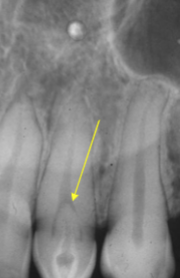

scalloping

radiolucent lesion that extends between the roots, seen in traumatic bone cyst (TBC)